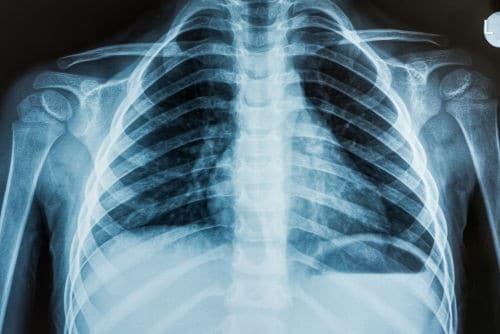

1-É assim que fica o pé quando a pessoa usa salto alto. Essa curvatura pode danificar nervos, tendões e articulações